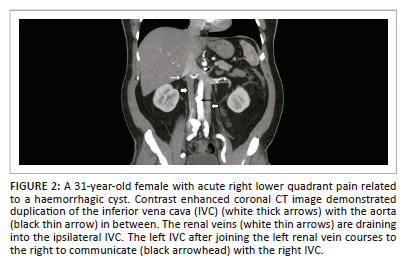

Although the posterior cardinal veins do not contribute to the adult IVC, abnormality in development of the posterior cardinal veins can lead to IVC anomalies.5 Anomalies in this complex process can lead to various congenital anomalies of the IVC, which has been reported in nearly 4% of the general population (Table 2).2 Associated congenital abnormalities can occur particularly in cases with azygos continuation of the IVC, which are related to heterotaxy syndrome with left isomerism.2,8

Most congenital anomalies are asymptomatic, but their identification is necessary to avoid mistaking them for pathology and for planning of vascular procedures (Table 3).13 Most of the congenital IVC abnormalities, particularly those that result in an abnormal vein or abnormal dilation of normal veins, can mimic lymphadenopathy.1

Left-sided inferior vena cava

Double inferior vena cava

Interruption of the inferior vena cava with azygos or hemiazygos continuation

Double inferior vena cava with retroaortic right renal vein and hemiazygos continuation of the inferior vena cava

Double inferior vena cava with a retroaortic left renal vein and azygos continuation of the inferior vena cava

The absence of the inferior vena cava